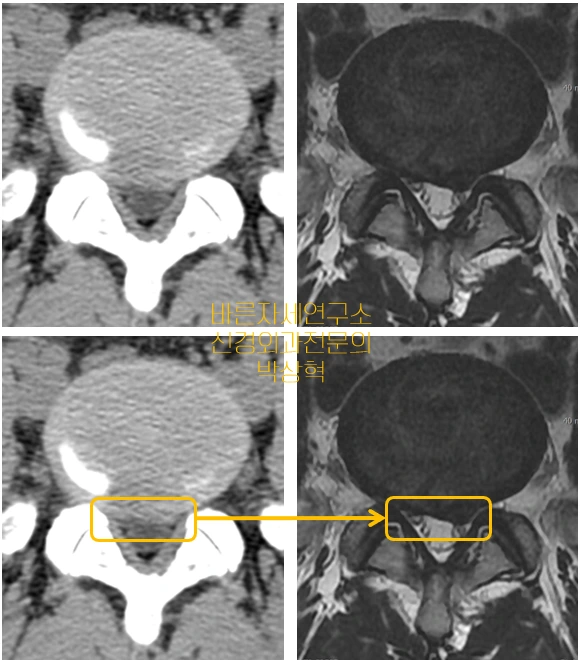

아래 사진도 비교해 보자.

image.png?type=w1

좌측의 CT 에서는 노란 사각형 안의 어느정도 밝은 음영이 보이지만 신경을 얼마나 누르는지 명확히 확인하기 어려운 반면 우측의 MRI 에서는 터진 디스크의 음영이 명확히 신경을 압박하는 것을 확인할 수 있다.

실제 외과 수술 전문의인 나의 소견으로도 좌측 CT 는 수술할 병변에 확신을 갖기 어렵지만 우측 MRI 에서는 디스크의 제거 필요성을 고민할 필요가 있음을 알 수 있다. 물론 수술여부는 영상만으로 결정하는 것이 아니다.